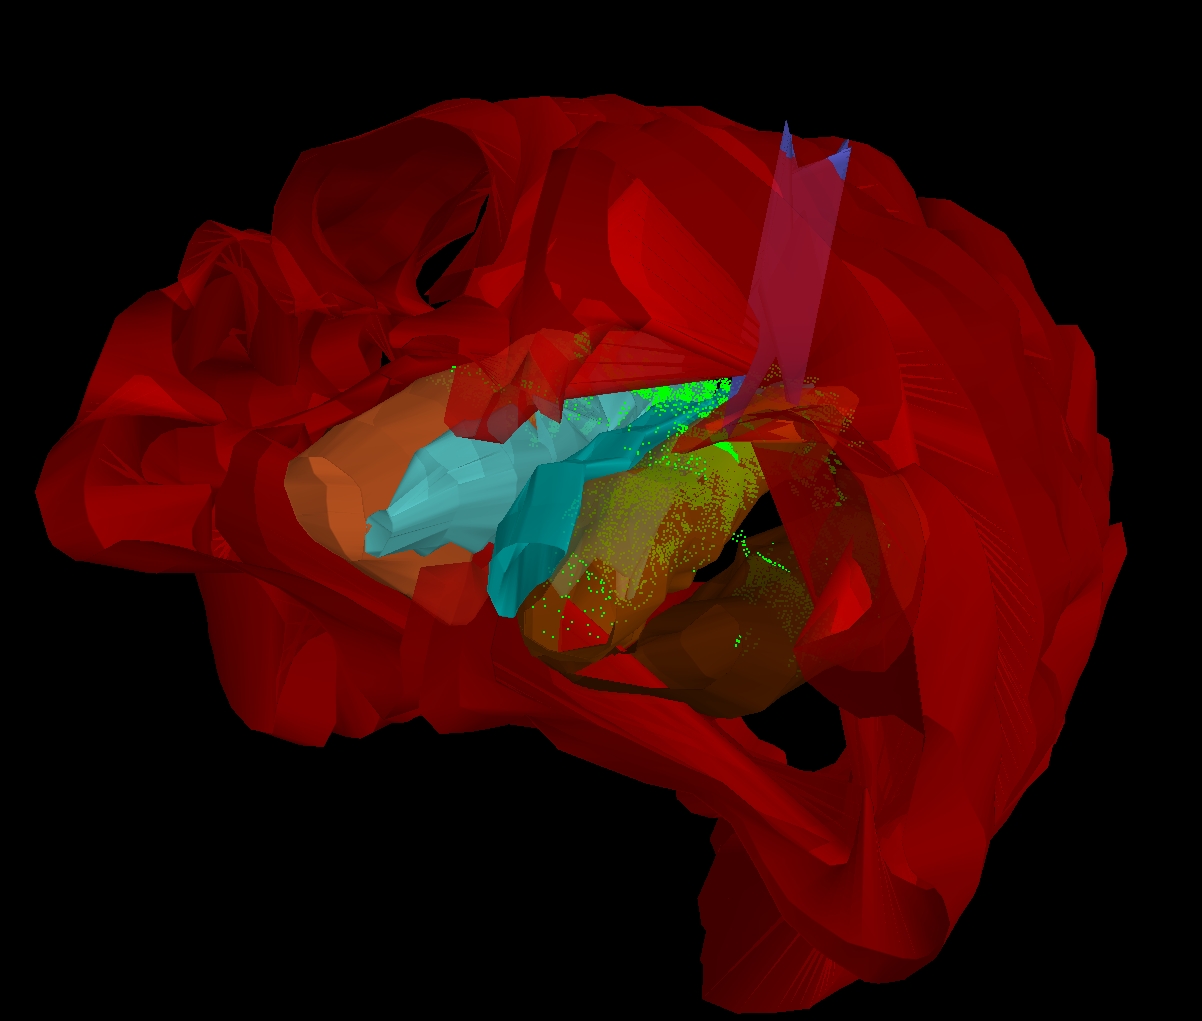

La stéréologie est une discipline scientifique qui permet d’estimer de manière objective et non biaisée des paramètres tridimensionnels (volume, surface, nombre, densité) à partir d’images bidimensionnelles, telles que des coupes histologiques ou microscopiques.

Elle repose sur des méthodes statistiques et géométriques éprouvées, largement utilisées en recherche biomédicale, en anatomopathologie, en neurosciences et en toxicologie. Les résultats obtenus par des méthodes stéréologiques sont reconnus pour leur robustesse et leur valeur scientifique.

Neurosciences